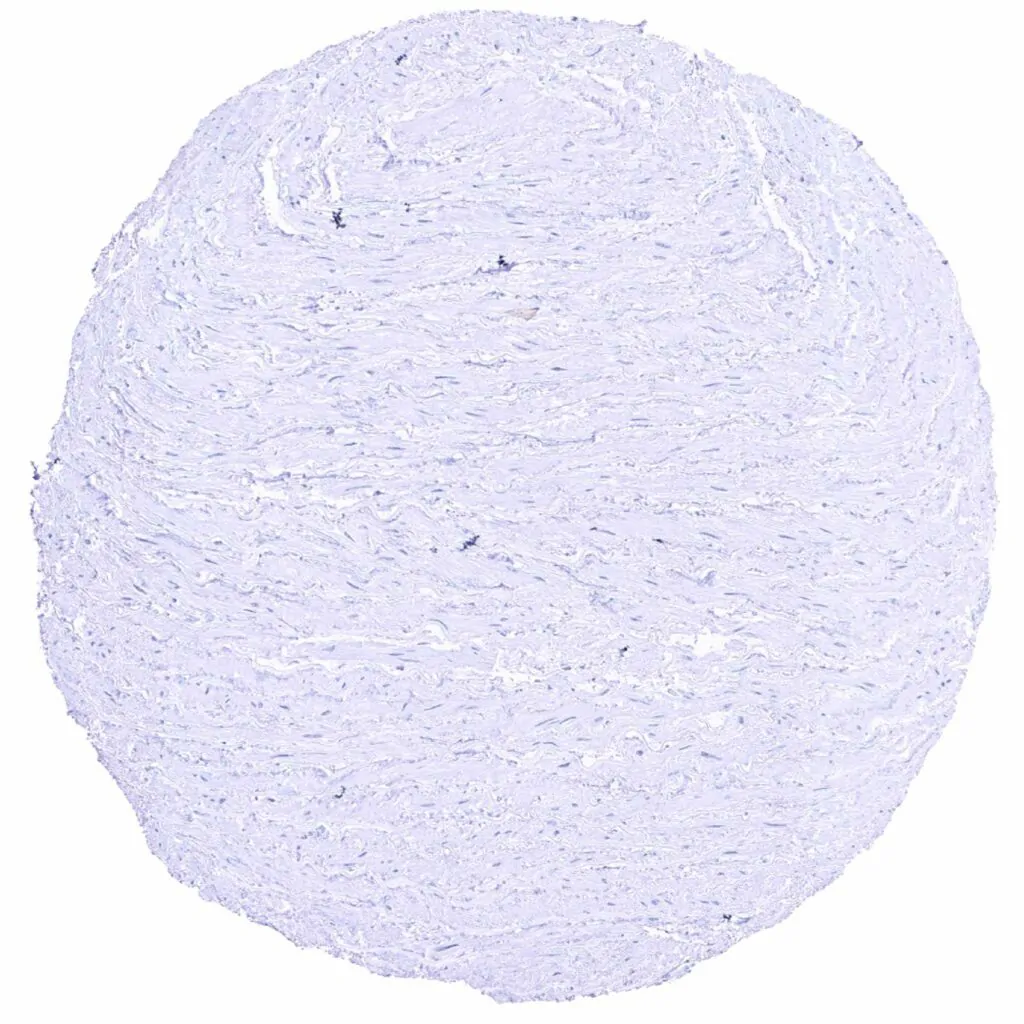

Uterus, myometrium